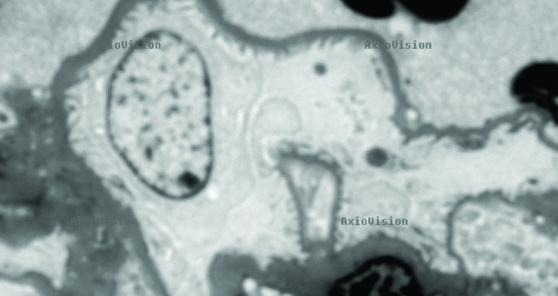

Human anterior pituitary, FIRM image taken with 150X glycerin objective. Individual secretory granules are easily visualized, ranging from 150- 350nm in diameter. Scale bar, 5µm.